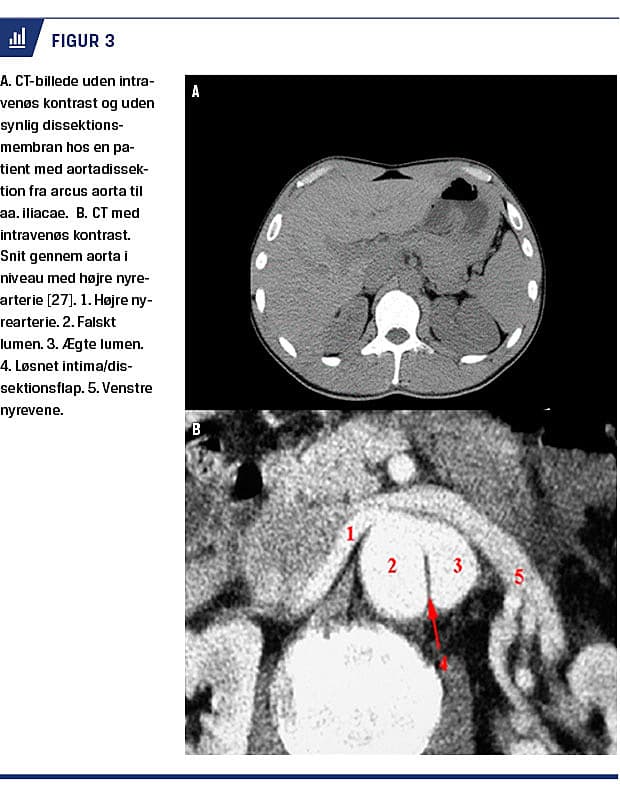

Udvikling af EKG-gated CT-angiografi skaber mulighed for endnu mere præcis diagnostik, da man med denne nye teknik kan fjerne pulsationsartefakter [2, 12]. I international litteratur anbefales herudover CT uden kontrast forud for en optimal kontrastundersøgelse for at kunne visualisere et evt. intramuralt hæmatom eller en forkalkning langs intima [10, 12] (Figur 3).